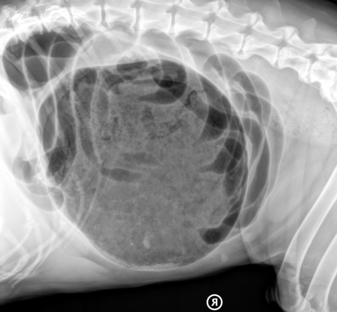

Melden Sie sich beim Vorliegen der oben genannten Symptome umgehend bei Ihrem Tierarzt. Dieser kann daraufhin den Hund klinisch untersuchen und ein Röntgenbild zur definitiven Diagnose anfertigen. Falls wirklich eine Magendrehung vorliegt, ist eine Operation nötig. Bei der Operation wird der Magen zuerst entgast und dann wieder in seine ursprüngliche Position zurückgedreht. Um ein erneutes Drehen des Magens zu verhindern, wird er zudem an der Bauchwand festgenäht.